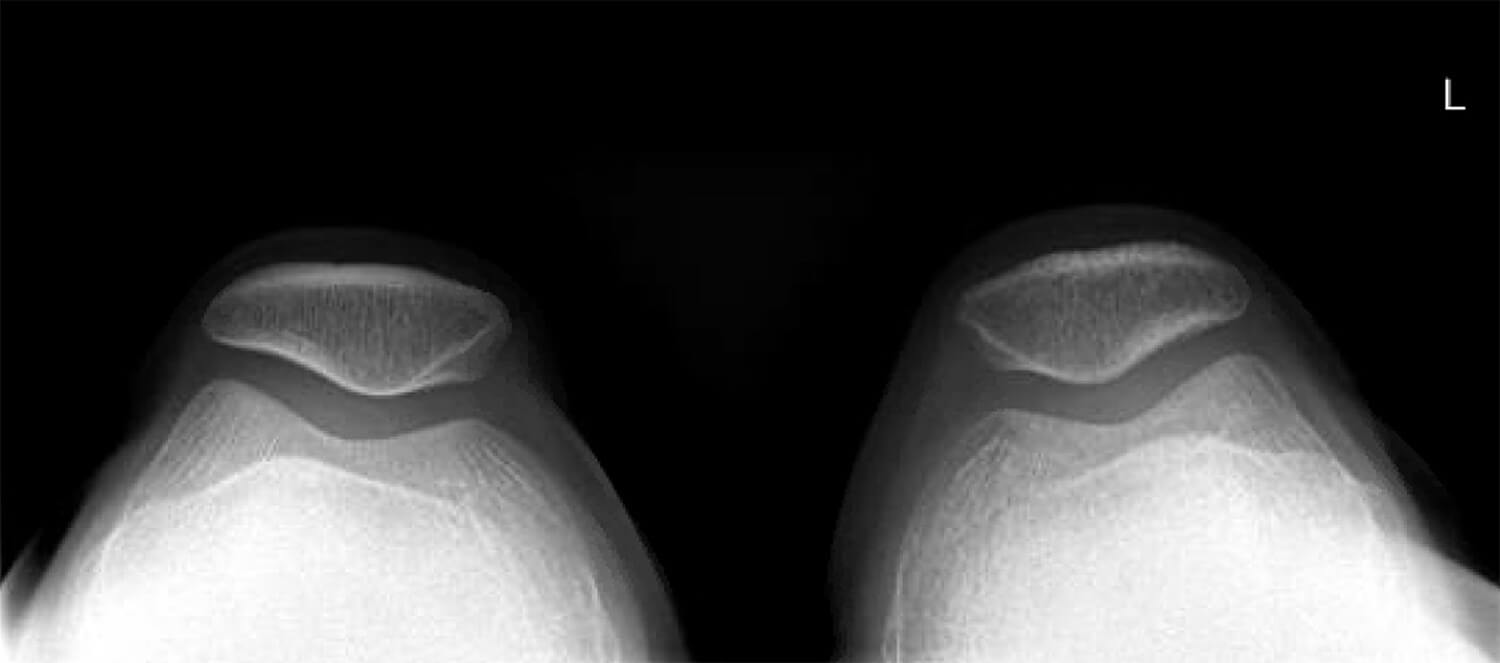

Met een röntgenfoto wordt gekeken naar de positie van de knieschijf ten opzichte van het bovenbeen. Door middel van dit onderzoek kan onder andere bekeken worden of de knieschijf niet te hoog staat (patella alta) of dat de knieschijf niet te veel naar buiten staat.

Een röntgenfoto van de bovenzijde genomen met een normale afstand van de knieschijf tot het bovenbeen en een normale positie.